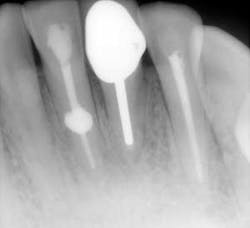

- Figures 9 and 10 show a discontinuation of the uniform outline of the pulpal chamber of tooth No. 19. Furthermore, margins of the lesion are sharp and well defined.

- Diagnosis: internal resorption.